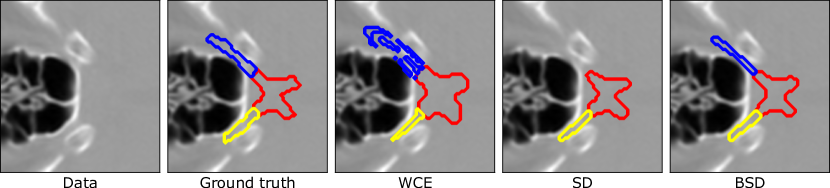

Refer to caption

Figure 1: Examples of optic nerves (blue, yellow) and chiasm (red) segmentation using various standard loss function such as weighted cross-entropy (WCE) and soft Dice (SD) and our Batch soft Dice (BSD) loss.

We first demonstrate the performance of the models on the case of optic nerves, optic chiasm, and brain stem segmentation. On other structures, the difference between performance of models trained with different loss functions is less significant. The results in terms of Dice coefficient (measure of segmentation quality on which the loss function is based) are shown in Figure 3. Superiority of soft Dice-trained models can be observed. However, standard soft Dice-trained model reaches a significantly smaller precision in case of optic nerves and sometimes misses the structure altogether as also illustrated by Figure 1. The model trained using the proposed batch soft Dice loss does not seem to suffer from this issue and we therefore conclude that it is more suitable for training models for segmentation of small anatomical structures with low contrast such as head and neck OAR.